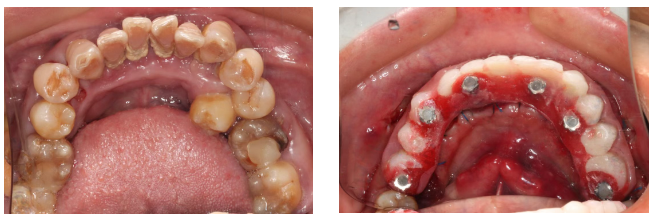

做手术前扫描制作导板,手术时缺牙位置切开一个小口,挖个小洞把种植体放进去,再缝一两针,操作简单,舒适感强。术后肿痛程度轻微。

伤口范围会扩大到周边牙齿,植入的骨粉材料会在半年内逐步替换成自身骨组织。伤口会红肿,疼痛感较强,部分人会出现脸颊淤青。

因此骨量严重不足时,需分次手术,植骨手术半年后视情况再行种植手术。

全口种植的患者骨量充足情况下,可以即刻种植,即刻修复,减少手术后的无牙时间,舒适感强。